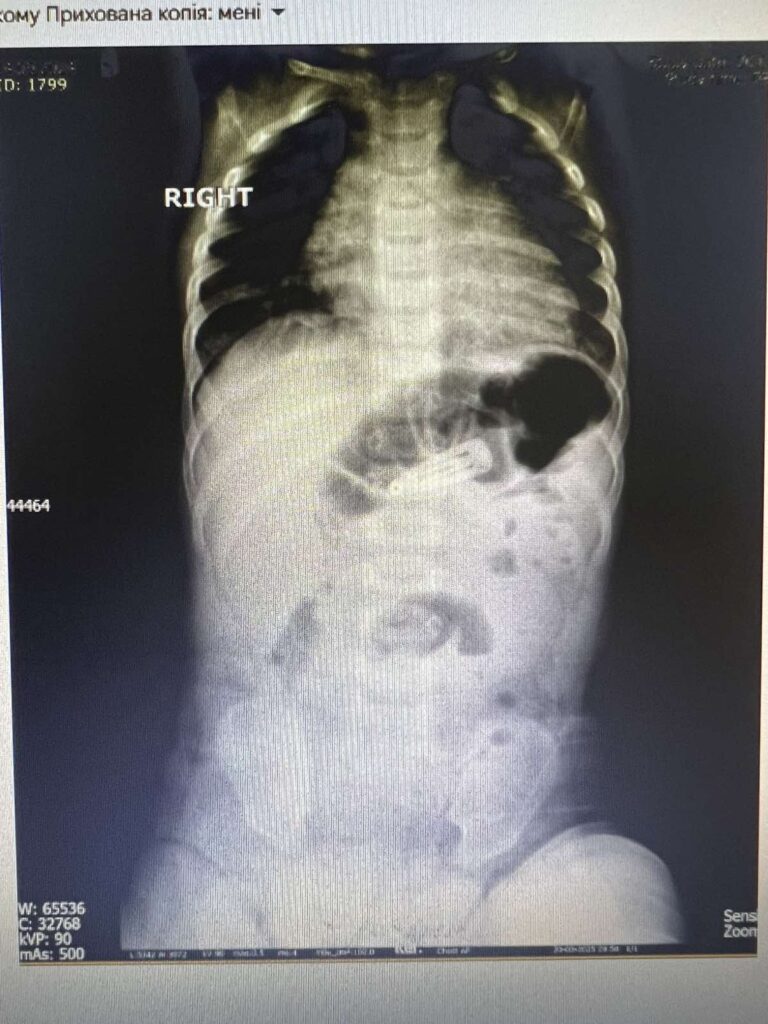

Дівчинка випадково проковтнула заколку для волосся. За таких обставин, враховуючи вік і масу тіла дитини (вага 7 кг), традиційно застосовується відкрите хірургічне втручання, однак це супроводжується вищим ризиком і тривалішим періодом відновлення.